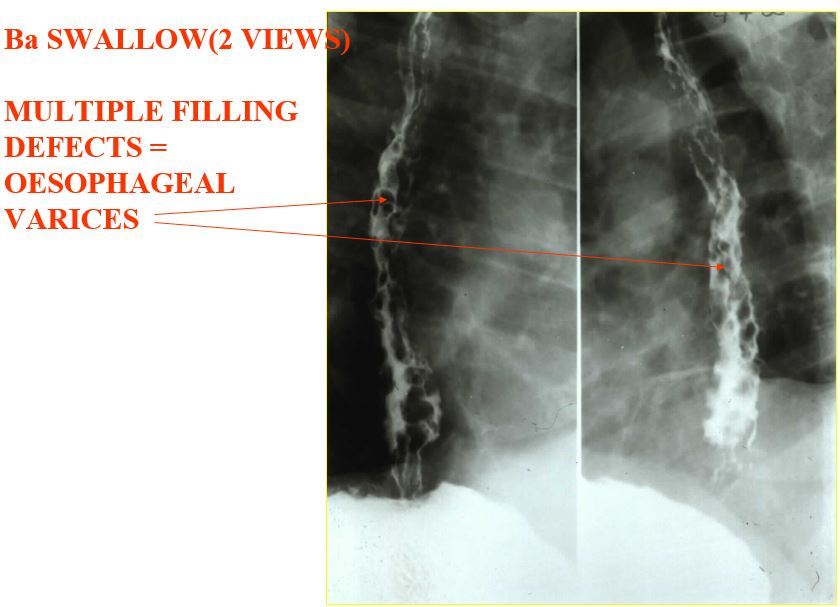

Image